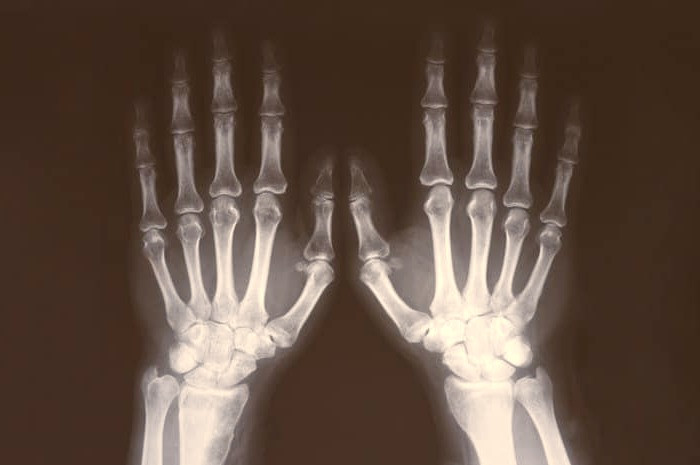

خانم ها بعد از 50 سال بیشتر در معرض خطر شکستگی استخوان و کاهش توده استخوان هایشان هستند؛ بنابراین باید سعی کنید که وضعیت خود را زیر نظر بگیرید.